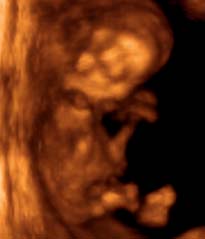

Terhességi naptár első trimeszter: 11. hét

A babád szervei most már tökéletesen végzik a dolgukat, van már csontváza, idegrendszere és vérkeringése is. A kicsi lábai elnyerték végleges formájukat, de még annyira aprók, hogy a körmödön is elférnének. Gyermeked túl van a fejlődés legkritikusabb szakaszán, mostantól leginkább az elképesztő sebességgel történő növekedésre, a szervek érésére és a születésre való felkészülésre kell koncentrálnia. Az elképesztő sebességű növekedést jól példázza, hogy a hét elején még csak kb. 21-25 mm hosszú, de a hét végére már elérheti a 44-51 mm-t és a 7 grammos súlyt is! És a testhosszba eddig még nem számoltuk bele a fej nagyságát. Az összenőtt szemhéjak alatt most alakul ki a gyerek írisze. Emellett fejlődnek a fogak, a körmök és a hajhagymák is.